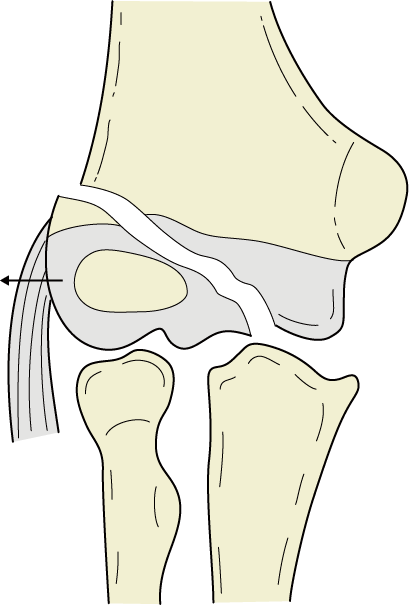

関節軟骨sleeve骨折

X線では外側上顆の小さい骨片としてしか写らないが、実際の骨片は上腕骨小頭の関節軟骨の75%を含んでいる、とAginsらが報告している。観血的整復の絶対的適応である。(イラストは一部改変)

出典

img

1: 井上博:小児四肢骨折治療の実際 改定第2版. 金原出版, 2001:99